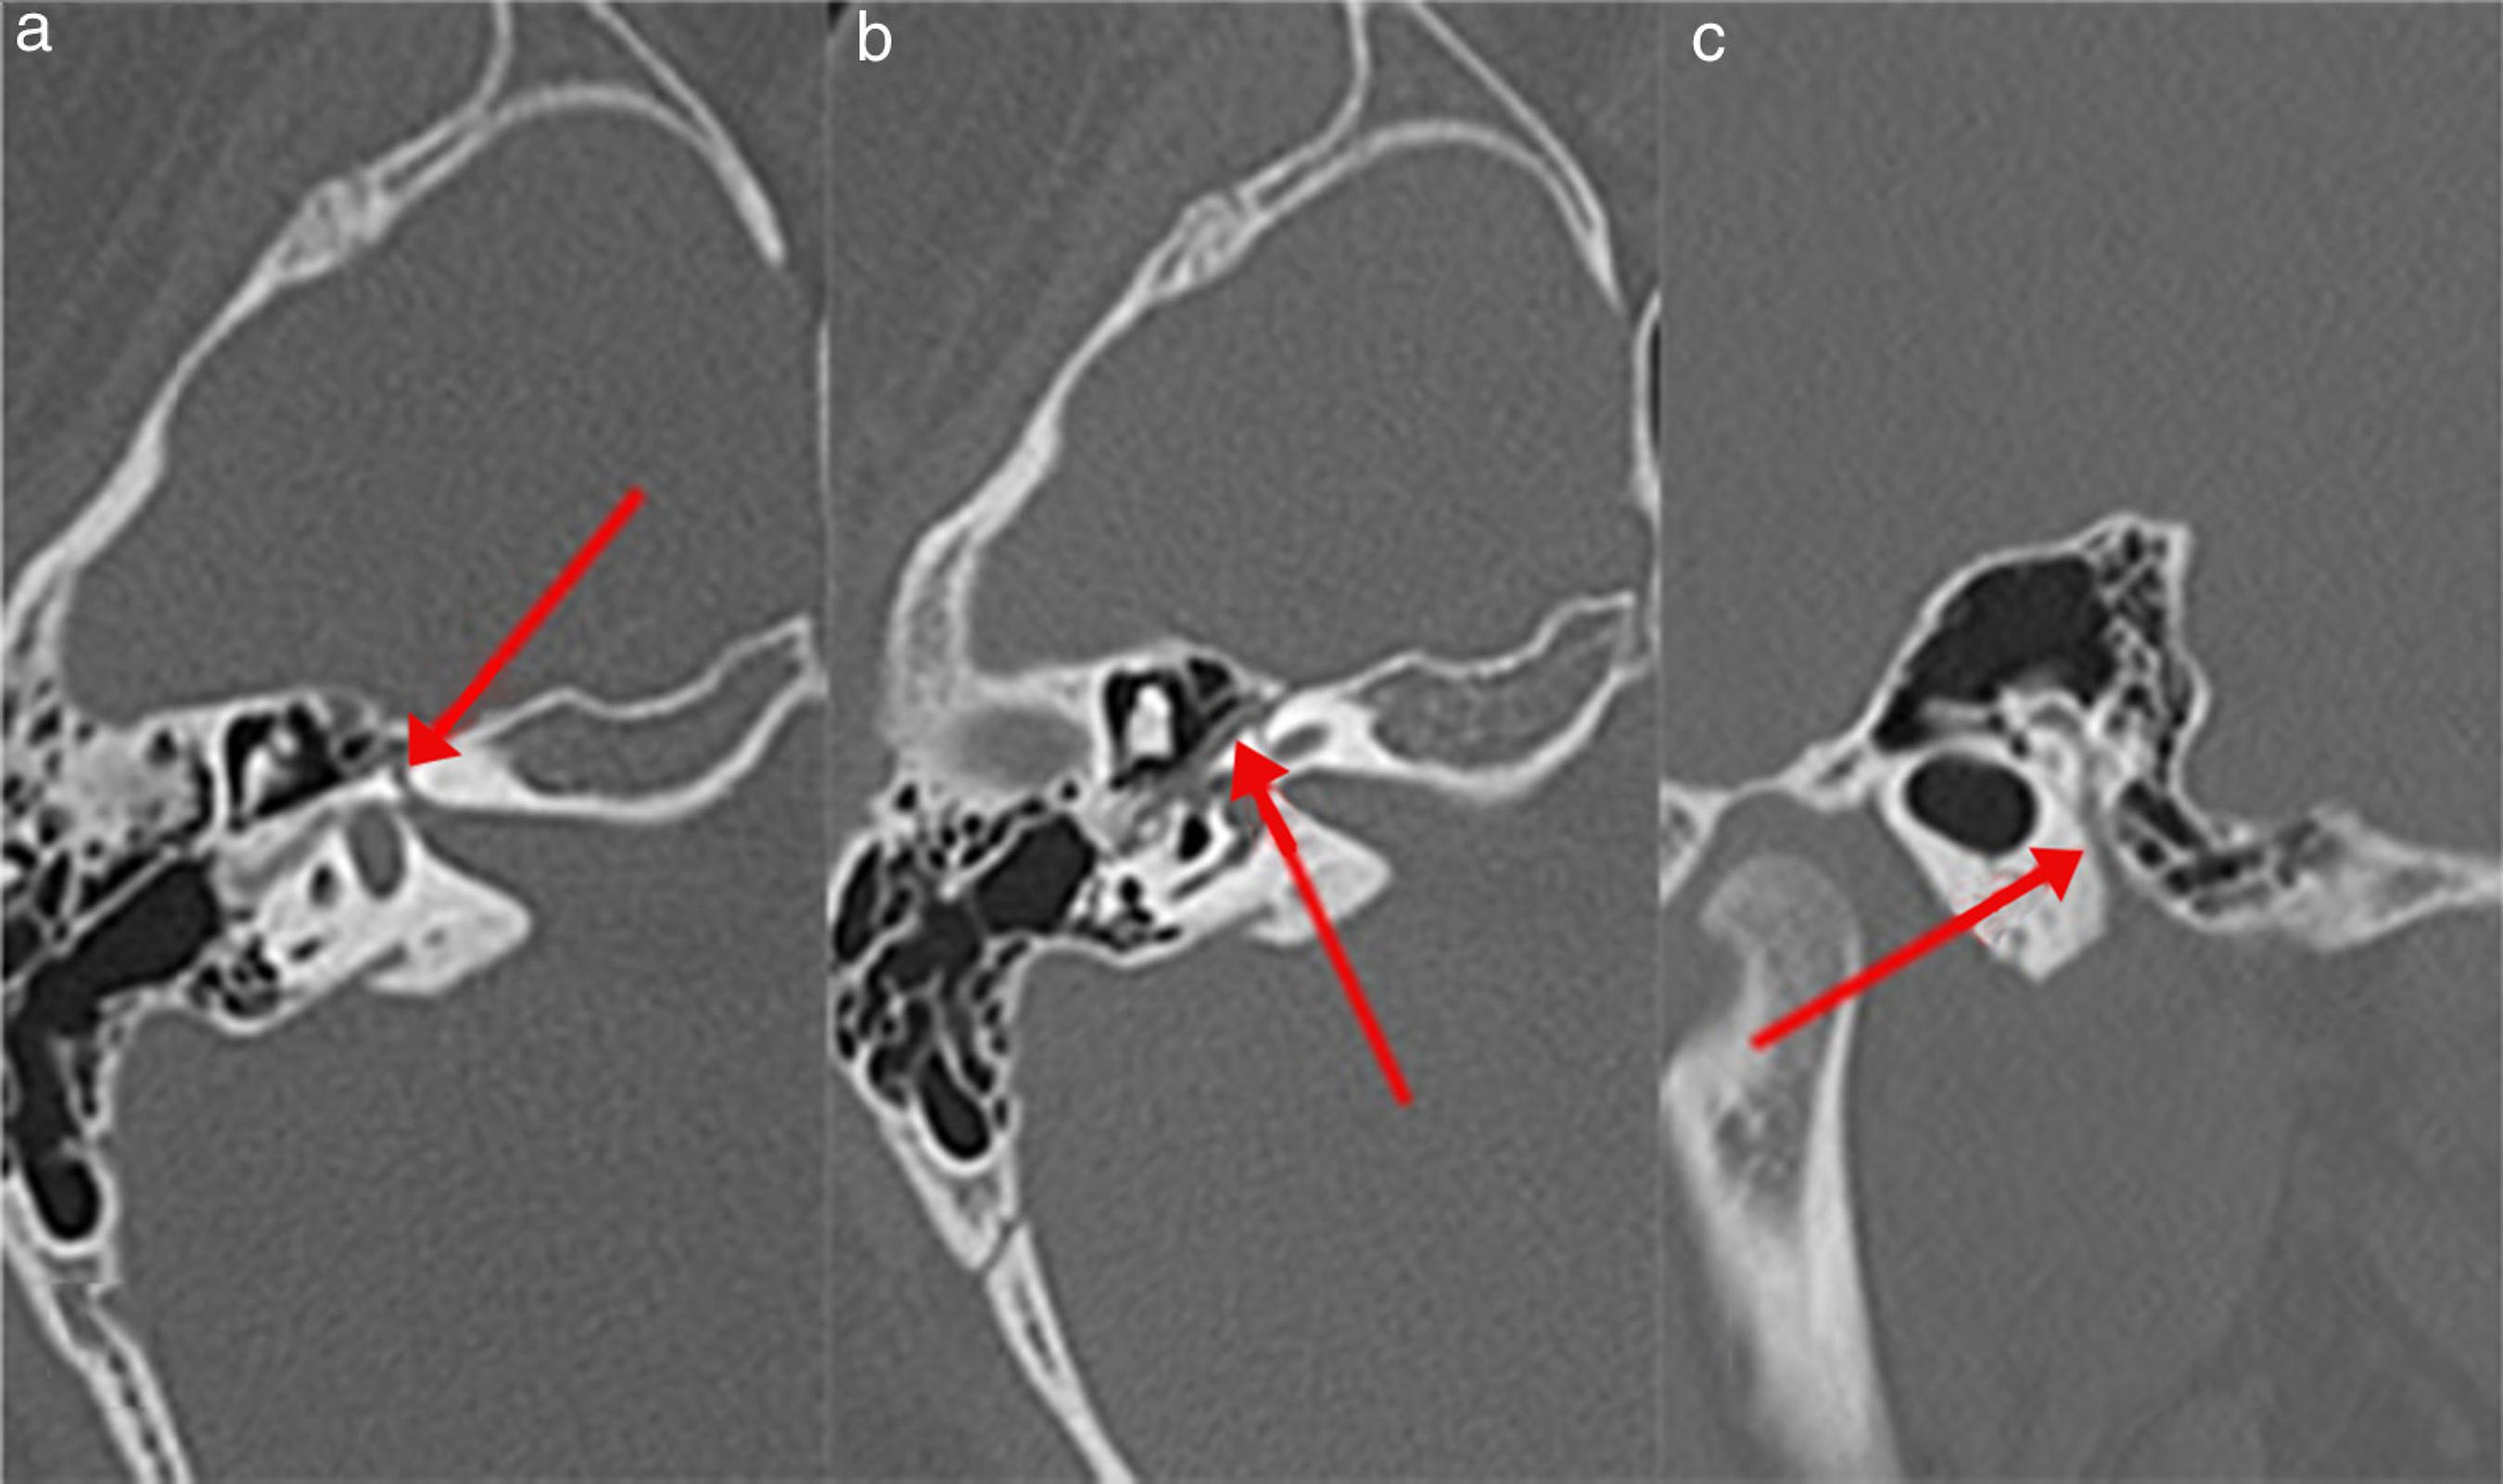

Лицевой нерв кт

Лицевой нерв кт 103 фото